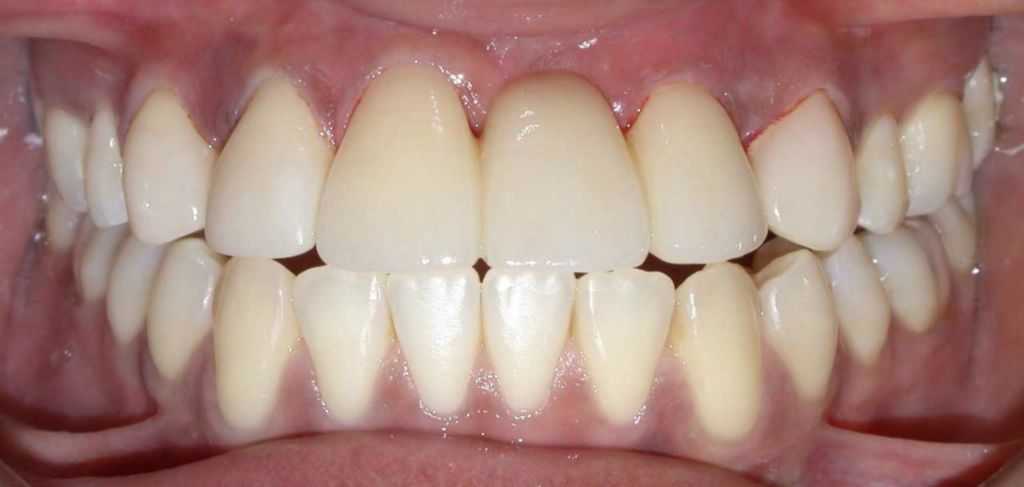

After

Before